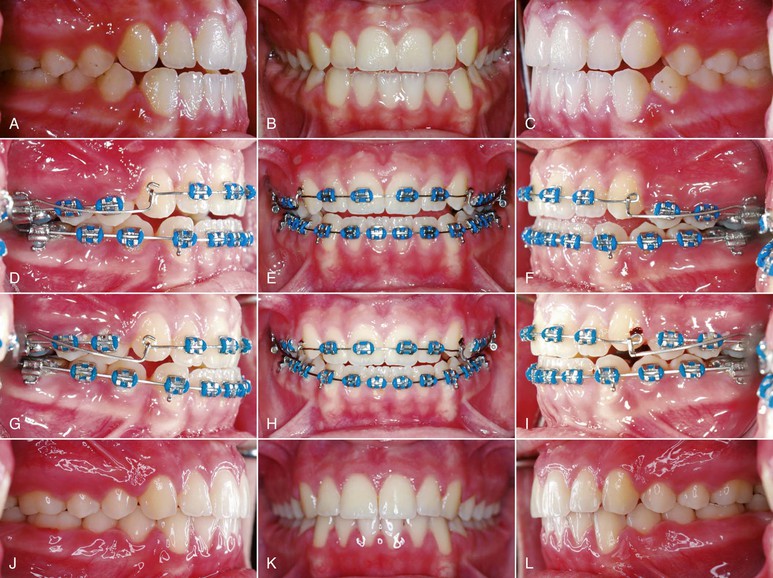

Different intraoral appliances are available for behavior modification. These appliances consist of a stiff archwire with a series of loops that sit closely to the anterior part of the palate and attach to two upper molar bands. The loops act as a mechanical obstruction and a reminder of the habit. Usually, after 3 months spontaneous correction of any dentoalveolar or eruption problem occurs without use of any other appliance (Fig. 9-8).

Figure 9-8 A–C, Patient with a finger-sucking habit resulting in an anterior open bite mesial to the first premolars. D, Lateral cephalogram showing characteristics of a dental open bite. E–H, Habit appliance with loops acting as a mechanical obstruction in close approximation to the anterior portion of the palate. I–K, Spontaneous correction of the anterior open bite after habit appliance delivery. L, Lateral cephalogram showing the open-bite closure. M, Superimposition reflecting the incisor extrusion that results with spontaneous closure of an anterior open bite with the habit appliance.